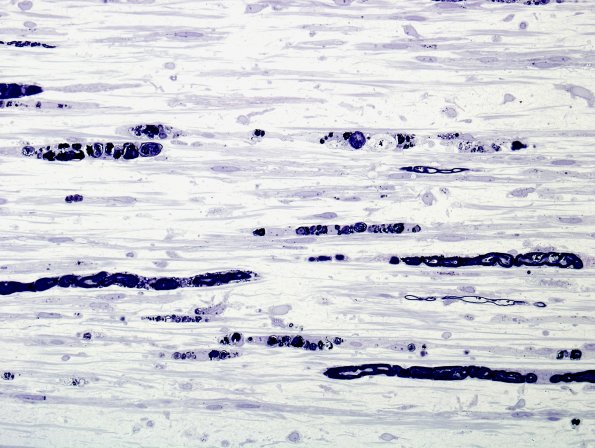

The same nerve as image #16A1 shown in longitudinal sections showing degenerating axon and myelin debris in Schwann cell ovoids. (plastic sections)